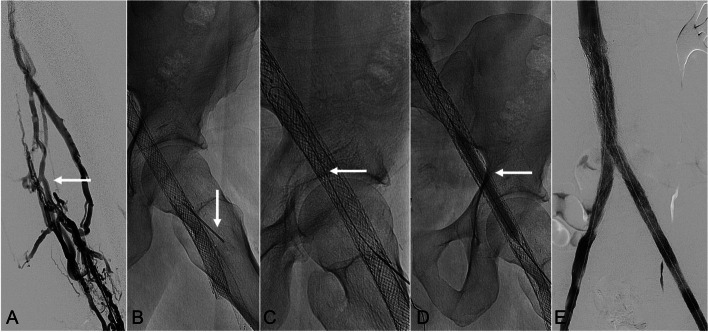

Direct percutaneous puncture of occluded venous stents as an adjunctive technique to restore patency.